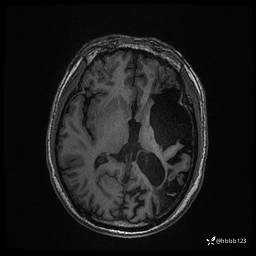

患者男,43岁。

简要病史:癫痫患者复诊,昨日发作5-6次,建议住院进一步治疗。

入院完善脑癫痫组合序列:

3d T1: